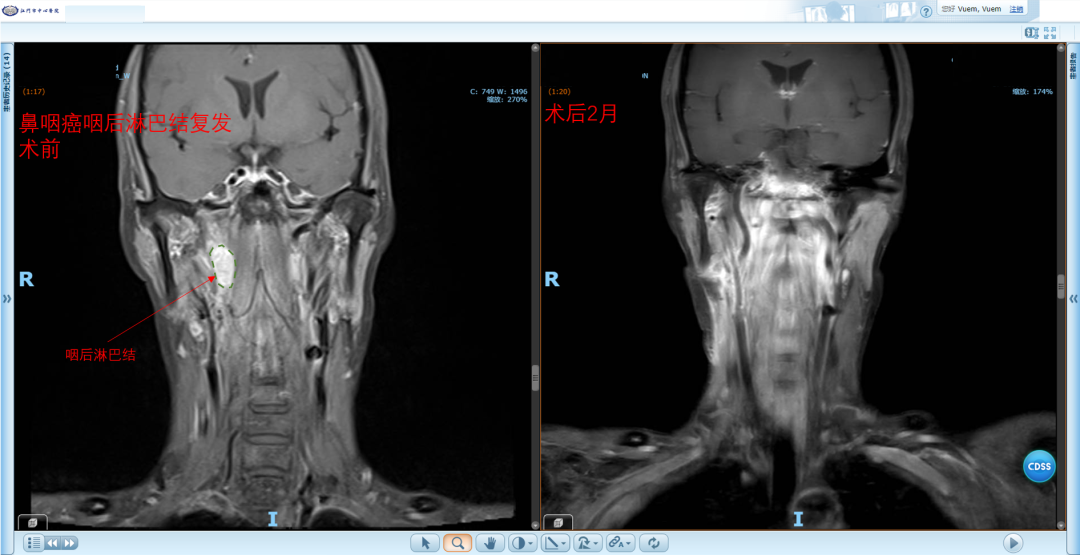

自2023年起,科室在五邑地区率先开展鼻内镜下复发性鼻咽癌切除及带蒂瓣修复术,为复发性鼻咽癌患者提供了优于二程放疗的治疗选择;随后,又陆续独立开展鼻内镜下翼腭窝、颞下窝及中颅窝底肿瘤切除术,进一步拓展了微创手术的技术边界;同期还成功完成五邑地区首例咽后淋巴结清扫术。这一系列技术突破,标志着我院在鼻咽-颅底领域的诊疗能力已达到了区域领先水平,也为复杂疾病患者带来了更为有效的治疗希望。